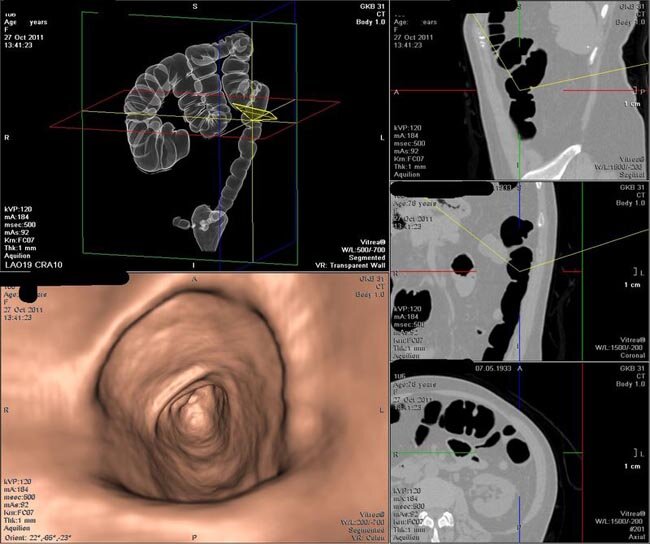

Виртуальная колоноскопия на компьютерном томографе в центре "Томоград" — высокоточная малоинвазивная методика обследования толстого кишечника

Это современная и малоинвазивная методика визуализации толстого кишечника, которая дает возможность точно определить локализацию патологического процесса, позволяет оценить состояние толстой кишки (вне зависимости от ее длины, наличия дополнительных петель).

Данный способ обследования основан на использовании мультиспиральной компьютерной томографии, в ходе которой на монитор передается 3D-изображение разных сегментов кишечника. Виртуальное исследование отличается от традиционной колоноскопии не только отсутствием необходимости во введении колоноскопа.

Методика проведения: процедура выполняется в амбулаторных условиях, исследование максимально комфортно для пациента. Продолжительность обследования — от 10 до 30 минут. Пациент размещается на кушетке. В прямую кишку вводится трубка, и нагнетается воздух для расправления стенок кишечника. Кушетка передвигается в сканер. Датчики внутри аппарата движутся вокруг пациента и выполняют серию снимков. По команде врача пациент должен задерживать дыхание.